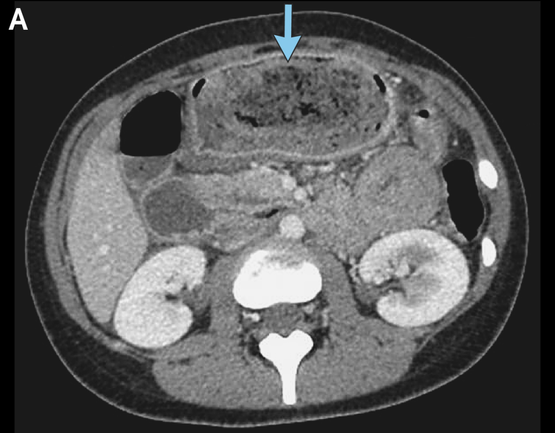

医生一一排查,把她腹痛、恶心呕吐的最可能原因集中到了两种疾病上。一种是消化性溃疡,因为患者近一周为缓解腰背痛吃了24片布洛芬。另一种是胃石,因为患者的长期用药中有两种会增加胃石形成的风险。接下来的胃镜检查给出了答案,医生在她的胃里看到了一大块胃石,诊断胃石症。

左滑查看更多图片:胃石示意图、手术中看到的毛发性胃石、CT检查中的胃石 | 参考文献[1]